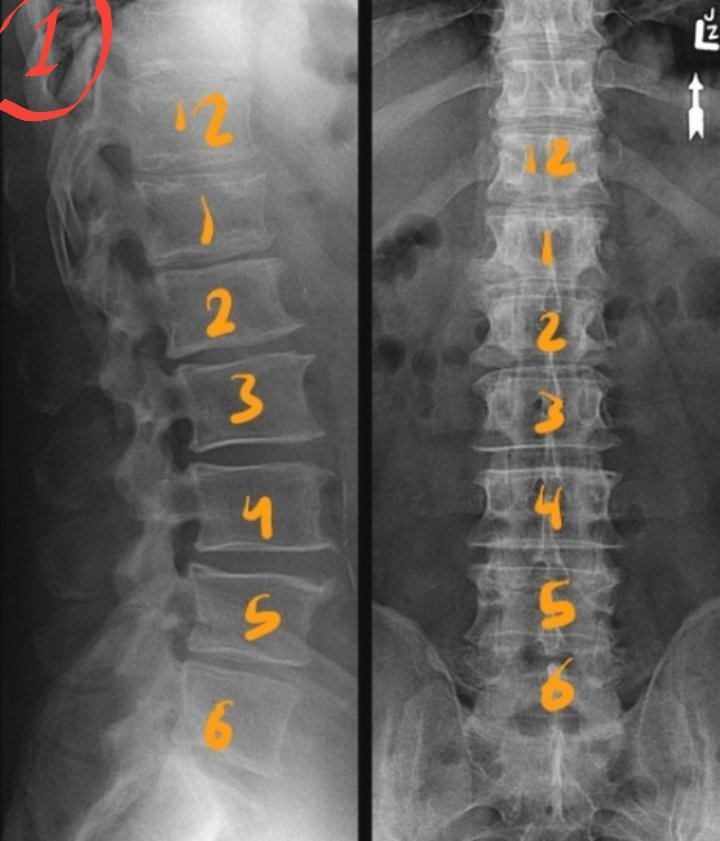

☆٥الفحص الأمامي للفقرات القطنية

AP view of Lumbar spine

معلومات/

•الفقرات القطنية عددها ٥ فقرات.

•أهم فقرة هي القطنية رقم ٣ ،لأنه يتم استخدامها كمركز للشعاع.

•يتم الاستدلال على موقعها بأنها تقع على مستوى حافة الأضلاع السفلى.

Lower costal margin

عدد الفقرات القطنية قد يختلف (مجازاً) عند بعض الأشخاص.

زيادتها إلى ٦ نتيجة عدم إلتحام العجزية الأولى بالثانية (s1-s2) فتظهر كأنها

٦فقرات قطنية

تسمى :

1.Lumbarisation

نقصانها إلى ٤ نتيجة إلتحام القطنية الخامسة بالعجزية الأولى فتظهر كأنه

٤فقرات قطنية

تسمى:

2.Sacralisation

الوضع:

المريض مستلقي على ظهره.

¤وضع prone أفضل للنساء لأنه يوفر حمايةإشعاعيةللمبايض بنسبة 25%-30%¤

•نتأكد أن الحوض غير ملتف أو مائل عن طريق ضبطه بالطلب من المريض أن يسترخي ثم نقوم بالإمساك بمنطقة أعلى الوركين ونرفعه عن الطاولة ثم إفلاته.

•ثني الركبتين وملامسة القدمين للطاولة.

الفائدة من ثني الركبتين وجعل القدمين تلامس الطاولة تقليل (الإنحناء) في الفقرات القطنية

(lordosis)

و حتى يصبح الدسك بين الفقرات موازي للشعاع.

التنفس/

يقوم بإخراج الهواء وايقاف التنفس.

السنتر CR/

L3

●تقييم الفلم/

نعرف عدم وجود إلتفاف

أنspinous process

في منتصف الفقرات✔

الوضع الجانبي للفقرات القطنية

Lateral view of Lumbar spine

تنبيهات/

•المسافة ١٢٠سم.

•يفضل أن يكون في وضعية الوقوف.

•لا تقلق من ظهور مساحة ضوء collimator

بشكل صغير على جسم المريض فقط تأكد أنه مفتوح بمقاس 43سم طولياً وهذا كاف.

•في الديجيتال غالباً ماتكون الصور سيئة بسبب خطأAEC.

سبب ظهور صورة lateral

بشكل باهت وسيء نابع من ٣أشياء:

١.السنتر الخاطئ للعضو على AEC cell

٢.تفعيل AEC الخاطئة.

٣.اختيار البروتوكول الخاطئ AP

بدل Lat.

•AEC

تقوم بقياس كمية الإشعاع الواصل للكاشف وتقوم بإيقافه عند وصول الكمية المناسبة.

فمالذي يحدث

اقرأ الملاحظات والصور المرفقة

لذلك إذا لم تضمن أن العمود الفقري يقع بداخل chamber الأوسط

بعد تفعيله اوتوماتيكياً عن طريق البروتوكول أو يدوياً.

فننصح بايقاف AEC و ادخال العوامل يدوياً.

•يجب ايقاف التنفس بعد إخراج الهواء.

مركز الشعاع/L3

انتهى Lumbar